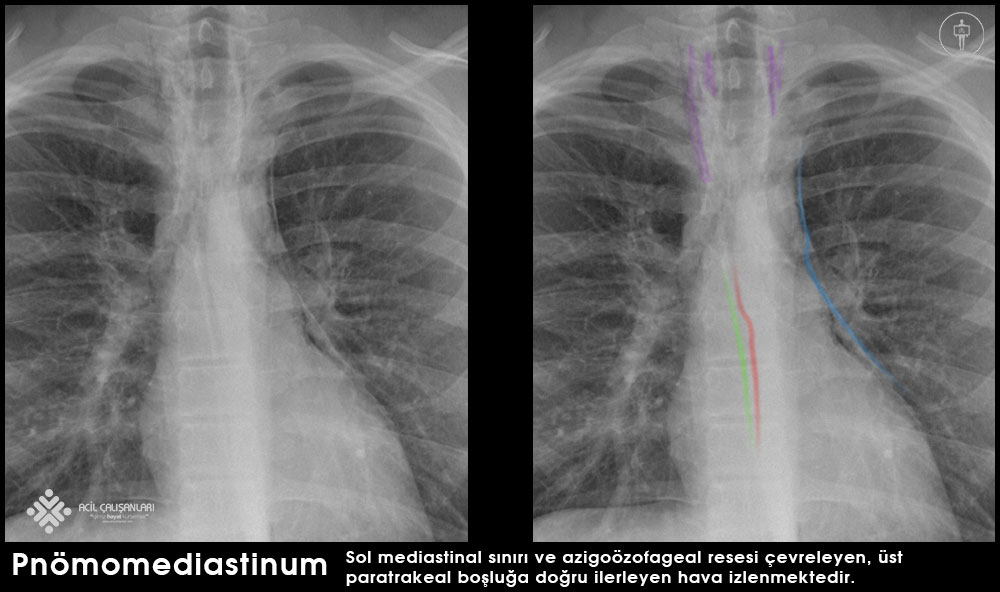

Pnömomediasten genellikle akciğer grafisi (PA akciğer grafisi) ile tanı alır. En sık görülen radyolojik bulgu, mediastinal yapıların etrafını saran havanın görülmesidir ve vakaların yaklaşık %90’ında saptanır. Lateral akciğer grafisi genellikle gerekli değildir.

Akciğer grafisinde görülebilecek diğer bulgular şunlardır:

- Subkutan amfizem

- Pediatrik hastalarda timusun yukarı doğru yer değiştirmesi (spinnaker sign)

- Pulmoner arterlerin etrafında hava görünümü (ring sign)

- İnferior aorta ile sol hemidiyafram arasında hipertransparan V şeklinde görünüm

- Çift bronş duvarı görünümü

- Continuous diaphragm sign (diyaframın kesintisiz görünmesi)

- Plevral efüzyon (özofagus yaralanmasını düşündürebilir)

Akciğer grafisi bulgularının şüpheli olduğu durumlarda toraks bilgisayarlı tomografisi (BT) pnömomediasteni kesin olarak doğrulamak veya dışlamak için kullanılabilir. BT, mediastende veya subkutan dokularda çok küçük miktardaki havayı bile saptayabilir. Ayrıca akciğer grafisinde ayırt edilmesi zor olabilen pnömomediasten ile pnömoperikardiyumu birbirinden ayırmada da yardımcıdır.